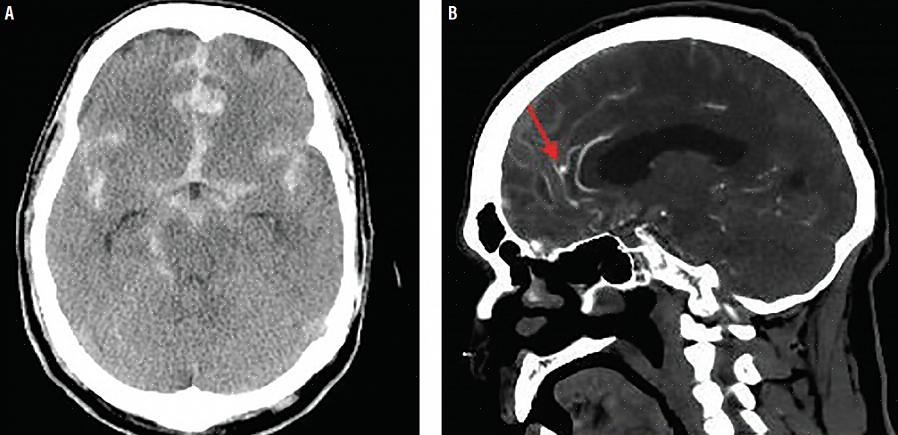

- בדיקת CT.

- אנגיוגרפיה מוחית.